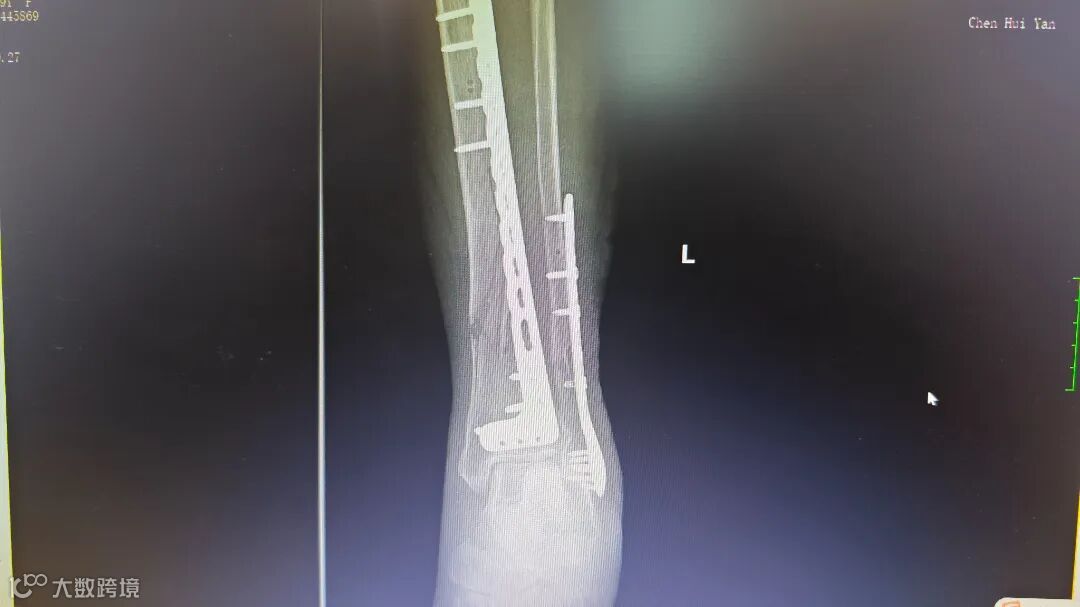

术后腿部影像

胸外科专家会诊后确认,患者肋骨骨折无明显位移,决定采用胸带固定配合卧床静养的保守治疗方案。针对更为复杂的小腿骨折,骨科团队在5月4日由张均锦主刀,曹桂青、陆仕邦医师协助下实施了精准复位手术。术中使用接骨板进行内固定后,X光显示骨折端对位良好,术后第三天患者已能进行简单的足部活动。